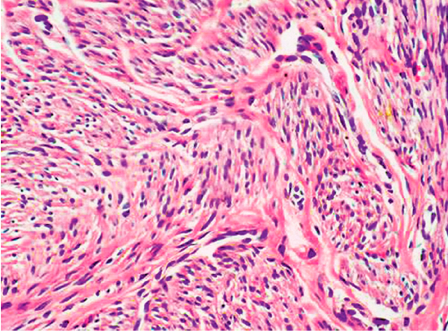

(2)镜下,瘤细胞与正常子宫平滑肌细胞相似,梭形,束状或旋涡状排列,胞浆红染,核呈长杆状,两端钝圆,核分裂少见,缺乏异型性。肿瘤与周围正常平滑肌界限清楚。

平滑肌瘤极少恶变,如肿瘤组织出现坏死,边界不清,细胞异型,核分裂增多,应诊断为平滑肌肉瘤(leiomyosarcoma)(如下图)。